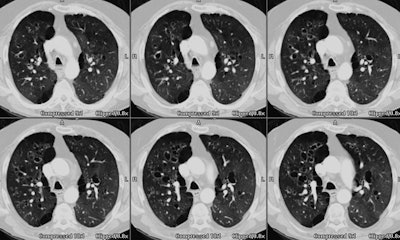

Case 3: Severe cystic bronchiectasis

The images from the CT scan below demonstrate extensive, severe cystic bronchiectatic changes. Allergic bronchopulmonary aspergillosis is a cause of cystic bronchiectasis. (Click image to enlarge)